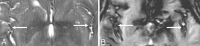

Despite extensive imaging, a source of bleeding is often not evident during the evaluation of patients with superficial siderosis (SS) of the central nervous system. An intraspinal fluid-filled collection of variable dimensions is frequently seen on spine MR imaging in patients with idiopathic SS. A similar finding has also been reported in patients with craniospinal hypotension. This review discusses the role of multitechnique imaging in the work-up of patients with SS and focuses on recent developments.